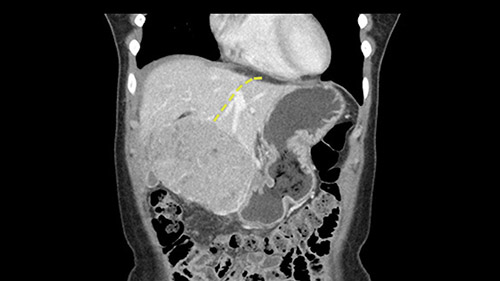

So if we look at the CT scan, on the axial, it’s a larger lesion. It’s about 6 or 7 or 8 centimeters. So it does look a bit threatening in terms of its resectability but if you really drill down deeply into the anatomy, and I think the coronal [imaging] is even better, you can see that the entire mass is on the patient’s left side of the falciform ligament. So it’s really only a left-sided tumor and not even really a left-sided tumor because Segment 4 is uninvolved anatomically.

None of the parenchyma is affected and this tumor is very exophytic; like many Hepatitis B hepatomas; and otherwise is resectable with either a wedge resection part of Segment 2-3 or a formal left lateral segmentectomy.

As I review the CT scan, we have both arterial and venous phases, the tumor is obvious. But I’ll start by saying that the liver itself does not appear to be cirrhotic to my eye. It’s got a normal contour and allied to that, that I do not see evidence of portal hypertension. The spleen is normal, there’s no collateral vessels. The tumor itself, I measured maximally at about 11 centimetres in diameter and I’m told the alpha fetoprotein is very high (over 10000), which is entirely consistent with this being a solitary hepatocellular carcinoma that is very exophytic. It seems to emanate off the inferior margin of Segment 3 (because that’s the falciform). I’ll start by saying that this is not transplantable. The tumor exceeds our guidelines for transplantation, but it's likely resectable based on normal liver and no portal hypertension.

The other thing I would do in this case is to certainly to assess the coronal phase as we can see in the coronal phase, this tumor looks like it's growing from Segment 3, and again I don’t think there’s involvement of the right side of the liver or even on Segment 4.